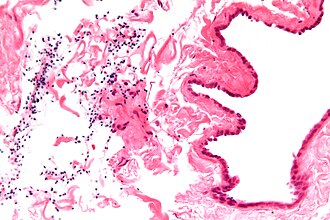

Spermatocele. H&E stain. | |

| LM | cyst lined by a simple ciliated epithelium, contain sperm |

- Cyst lined by a simple ciliated epithelium.

- Contain sperm.

- Head: ~1/2 the size of a RBC, black.

- Tail: infrequently seen.